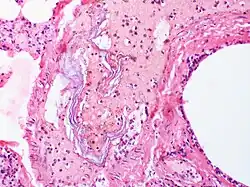

| Intravascular squames are present in this example of amniotic fluid embolism. | |